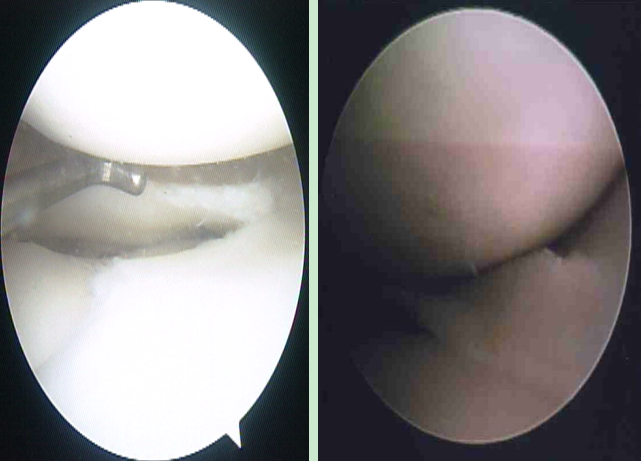

盤狀半月板的切除-鏡下解剖

v盤狀是畫盤的盤,象蠶豆,不是園盤的盤。由于緊挨者ACL,前角處有梨把凹陷與ACL緊密相貼。外側(cè)有腘肌腱和滑膜緣關(guān)節(jié)囊,前后角都基本在中線前后1/3處。

v所以要以ACL、腘肌腱、外緣關(guān)節(jié)囊為解剖標志,隔開ACL、腘肌腱,而外緣留多少無所謂,注意ACL、腘肌腱的損傷。外緣用刨刀再處理。

v通過改變器械進入的角度、器械本身的彎曲來完成,直剪用處很大,結(jié)合左右彎藍鉗或推鉤刀切除

桶柄裂

探察桶柄裂

桶柄裂取出